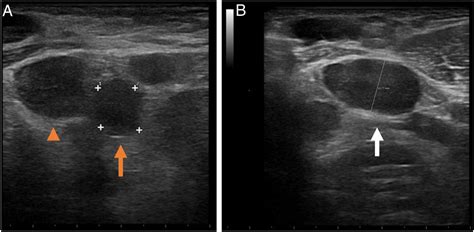

In some cases, a biopsy of the Hilar Lymph Nodes may be necessary to confirm a diagnosis. This procedure involves removing a small sample of the lymph node tissue for laboratory analysis. The results of the biopsy can help determine the presence and type of infection or cancer, guiding the appropriate treatment.

• Biopsy: In some cases, a biopsy of the Hilar Lymph Nodes may be necessary to confirm a diagnosis. This procedure involves removing a small sample of the lymph node tissue for laboratory analysis.

These diagnostic procedures are often used in combination to provide a comprehensive assessment of the Hilar Lymph Nodes and any underlying conditions.